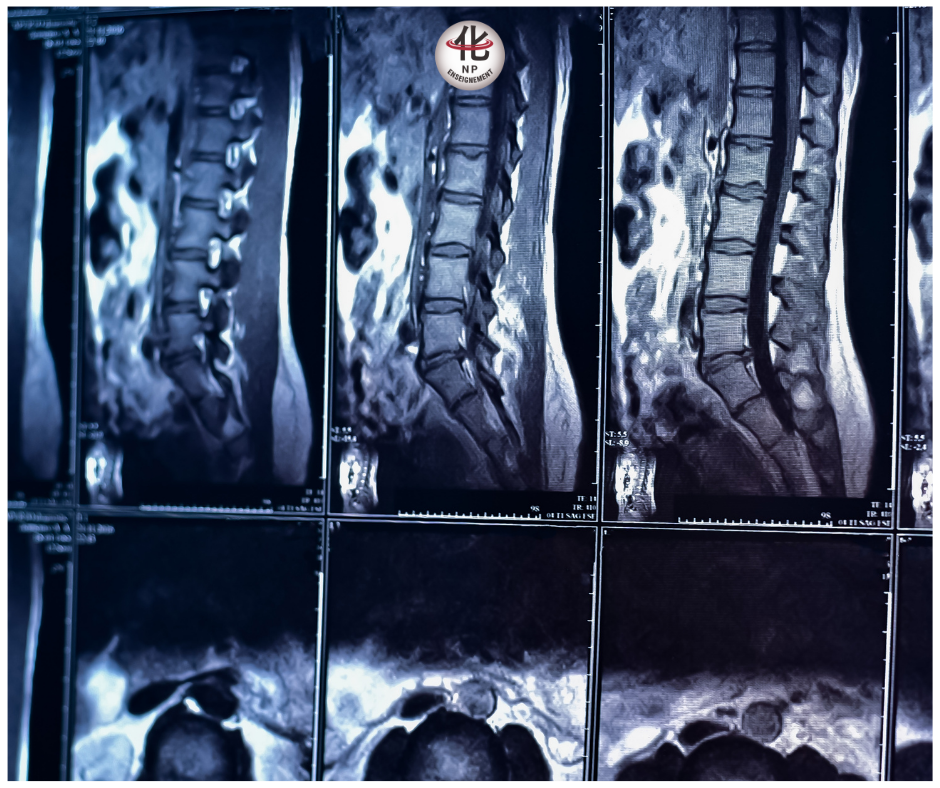

Lorsque vous consultez pour une douleur lombaire, il est fréquent que le médecin prescrive une radiographie, un scanner ou une IRM pour explorer la colonne vertébrale.

Une radiographie ou une IRM est une photographie — 2D ou 3D — de l’anatomie à un instant précis.

Cela montre clairement que l’imagerie seule ne rend pas compte des mécanismes fonctionnels et adaptatifs du corps.

Les examens d’imagerie anatomique sont statiques. Ils ne décrivent pas la façon dont le corps bouge, esquive, s’adapte ou évite une zone douloureuse.

Imagerie dynamique : scanner volumique

Il existe aujourd’hui des scanners capables d’intégrer le mouvement dans l’analyse, appelés scanners volumiques dynamiques.

Ces appareils — rares en France — permettent de visualiser la colonne en mouvement sous charge.

Ils confirment l’importance de regarder le corps en mouvement, et pas seulement en posture fixe.

Un bilan radiologique normal n’élimine pas la douleur.

Il montre simplement que la cause n’est pas visible dans un instant figé.